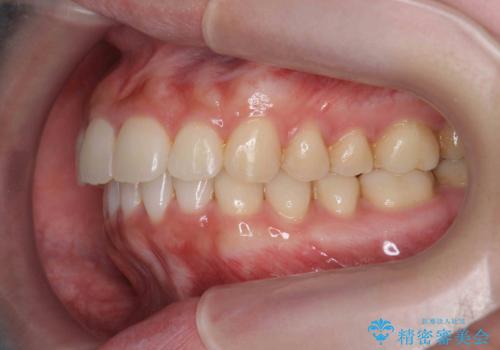

マウスピース 狭窄歯列の改善

- 噛み合わせが深い、笑った時の歯並びの改善を求めて来院されました。

マウスピース型の矯正装置インビザラインを用いた治療を計画します。

狭くなってしまった歯並びを放物線状に並べることで噛み合わせの安定・見た目の改善・ガタつきの改善を達成することができました。